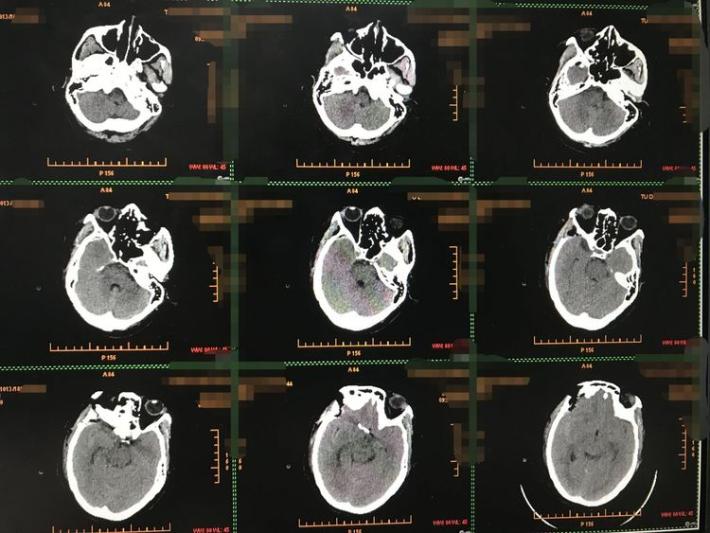

术后CT示术野干净,无出血或梗塞。